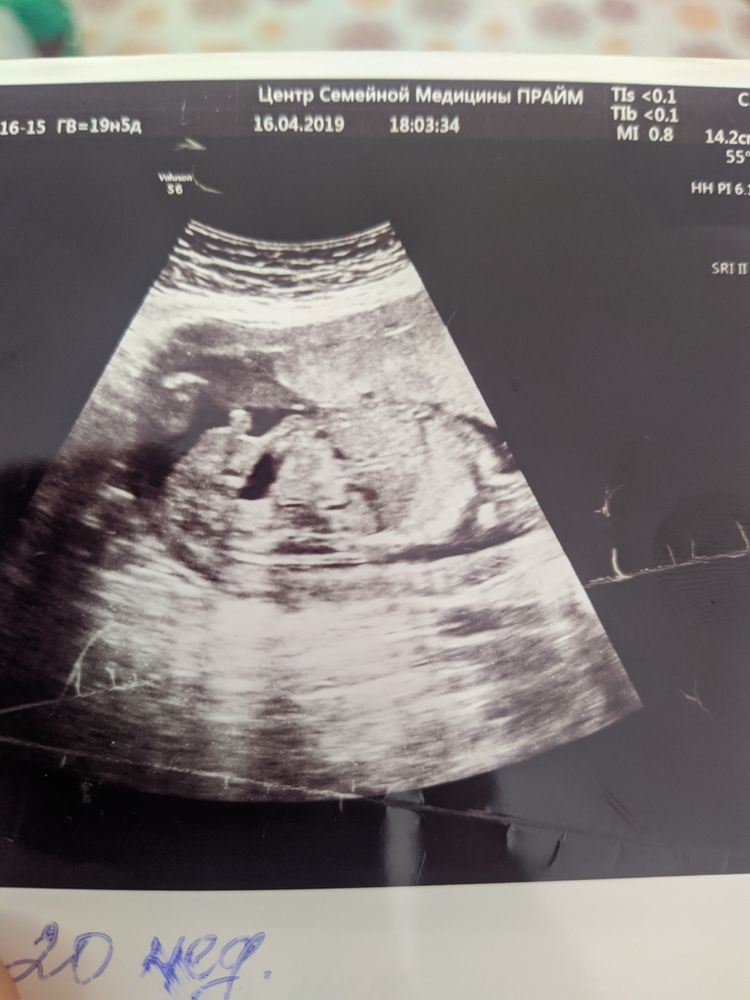

Татьяна, вот снимок прошлой беременности ,родила мальчика.тут сразу видно торчит вверх